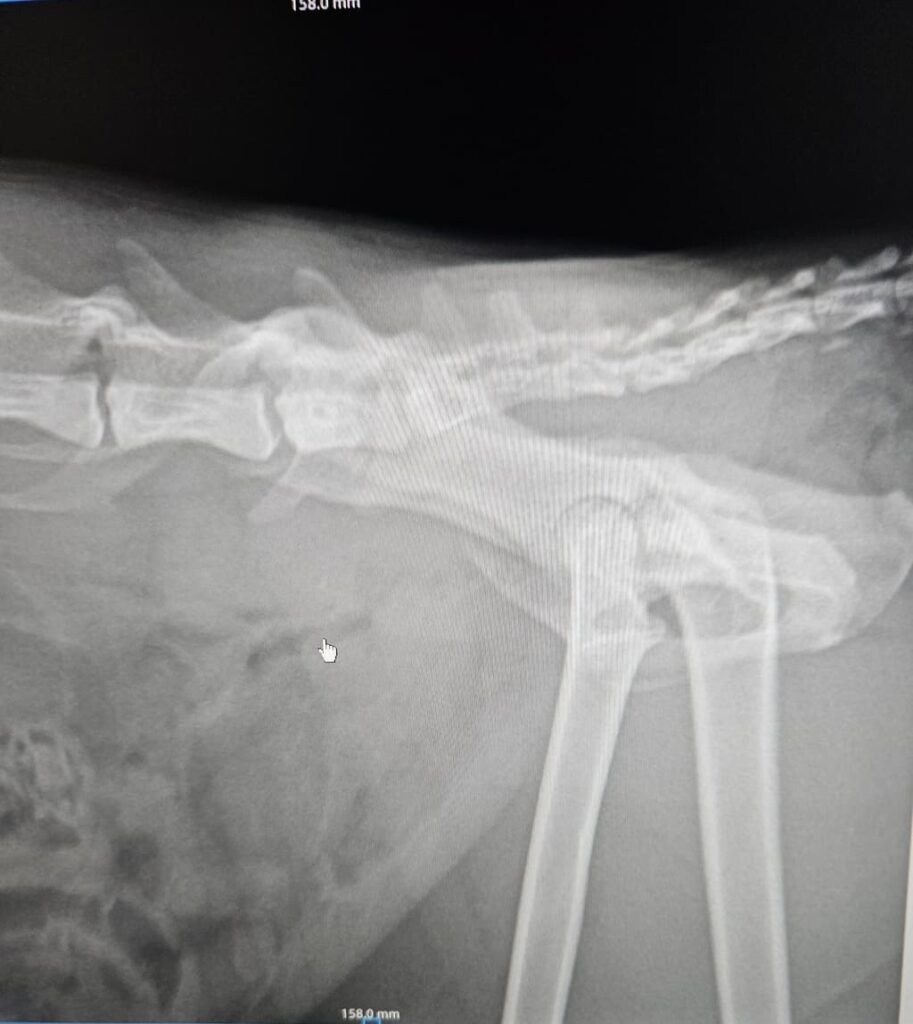

Le condizioni del povero micio

Il micio trovato investito e abbandonato in strada dovrà subire un intervento. Ha anche la vescica lacerata. Abbiamo bisogno di soldi, da soli non possiamo farcela, la cifra è alta.